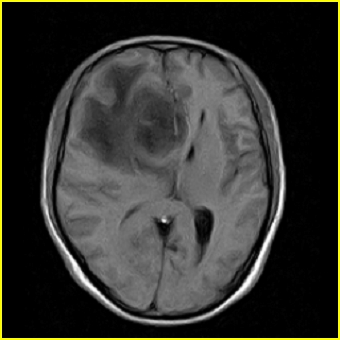

男,45岁,头部剧烈疼痛伴呕吐5天。

右侧额叶见较大的类圆形长t1信号环绕等t1环影,长t2信号环绕短等t2环,周围见明显水肿占位征,中线结构左移,男,45岁,头部剧烈疼痛伴呕吐5天。

病灶紧贴大脑镰,周围见有大片水肿,考虑:1.脑膜瘤伴水肿,2.胶质瘤。

右侧额叶,见一占位病灶,t1像病灶、水肿长t1;其间为短t1环行信号。t2像病灶、水肿长t2,其间为短t2环行信号。占位效应明显,中线左移,右测脑室受压闭塞。结合患者发病较急。首先考虑:右侧额叶脑脓肿形成。鉴别:1、转移瘤,多发多见2、胶质瘤。建议增强

t1加权肿瘤呈低信号,肿瘤壁呈等信号.t2 加权时肿瘤呈高信号,肿瘤壁呈等信号.

考虑1脑脓肿.2恶性胶质瘤.